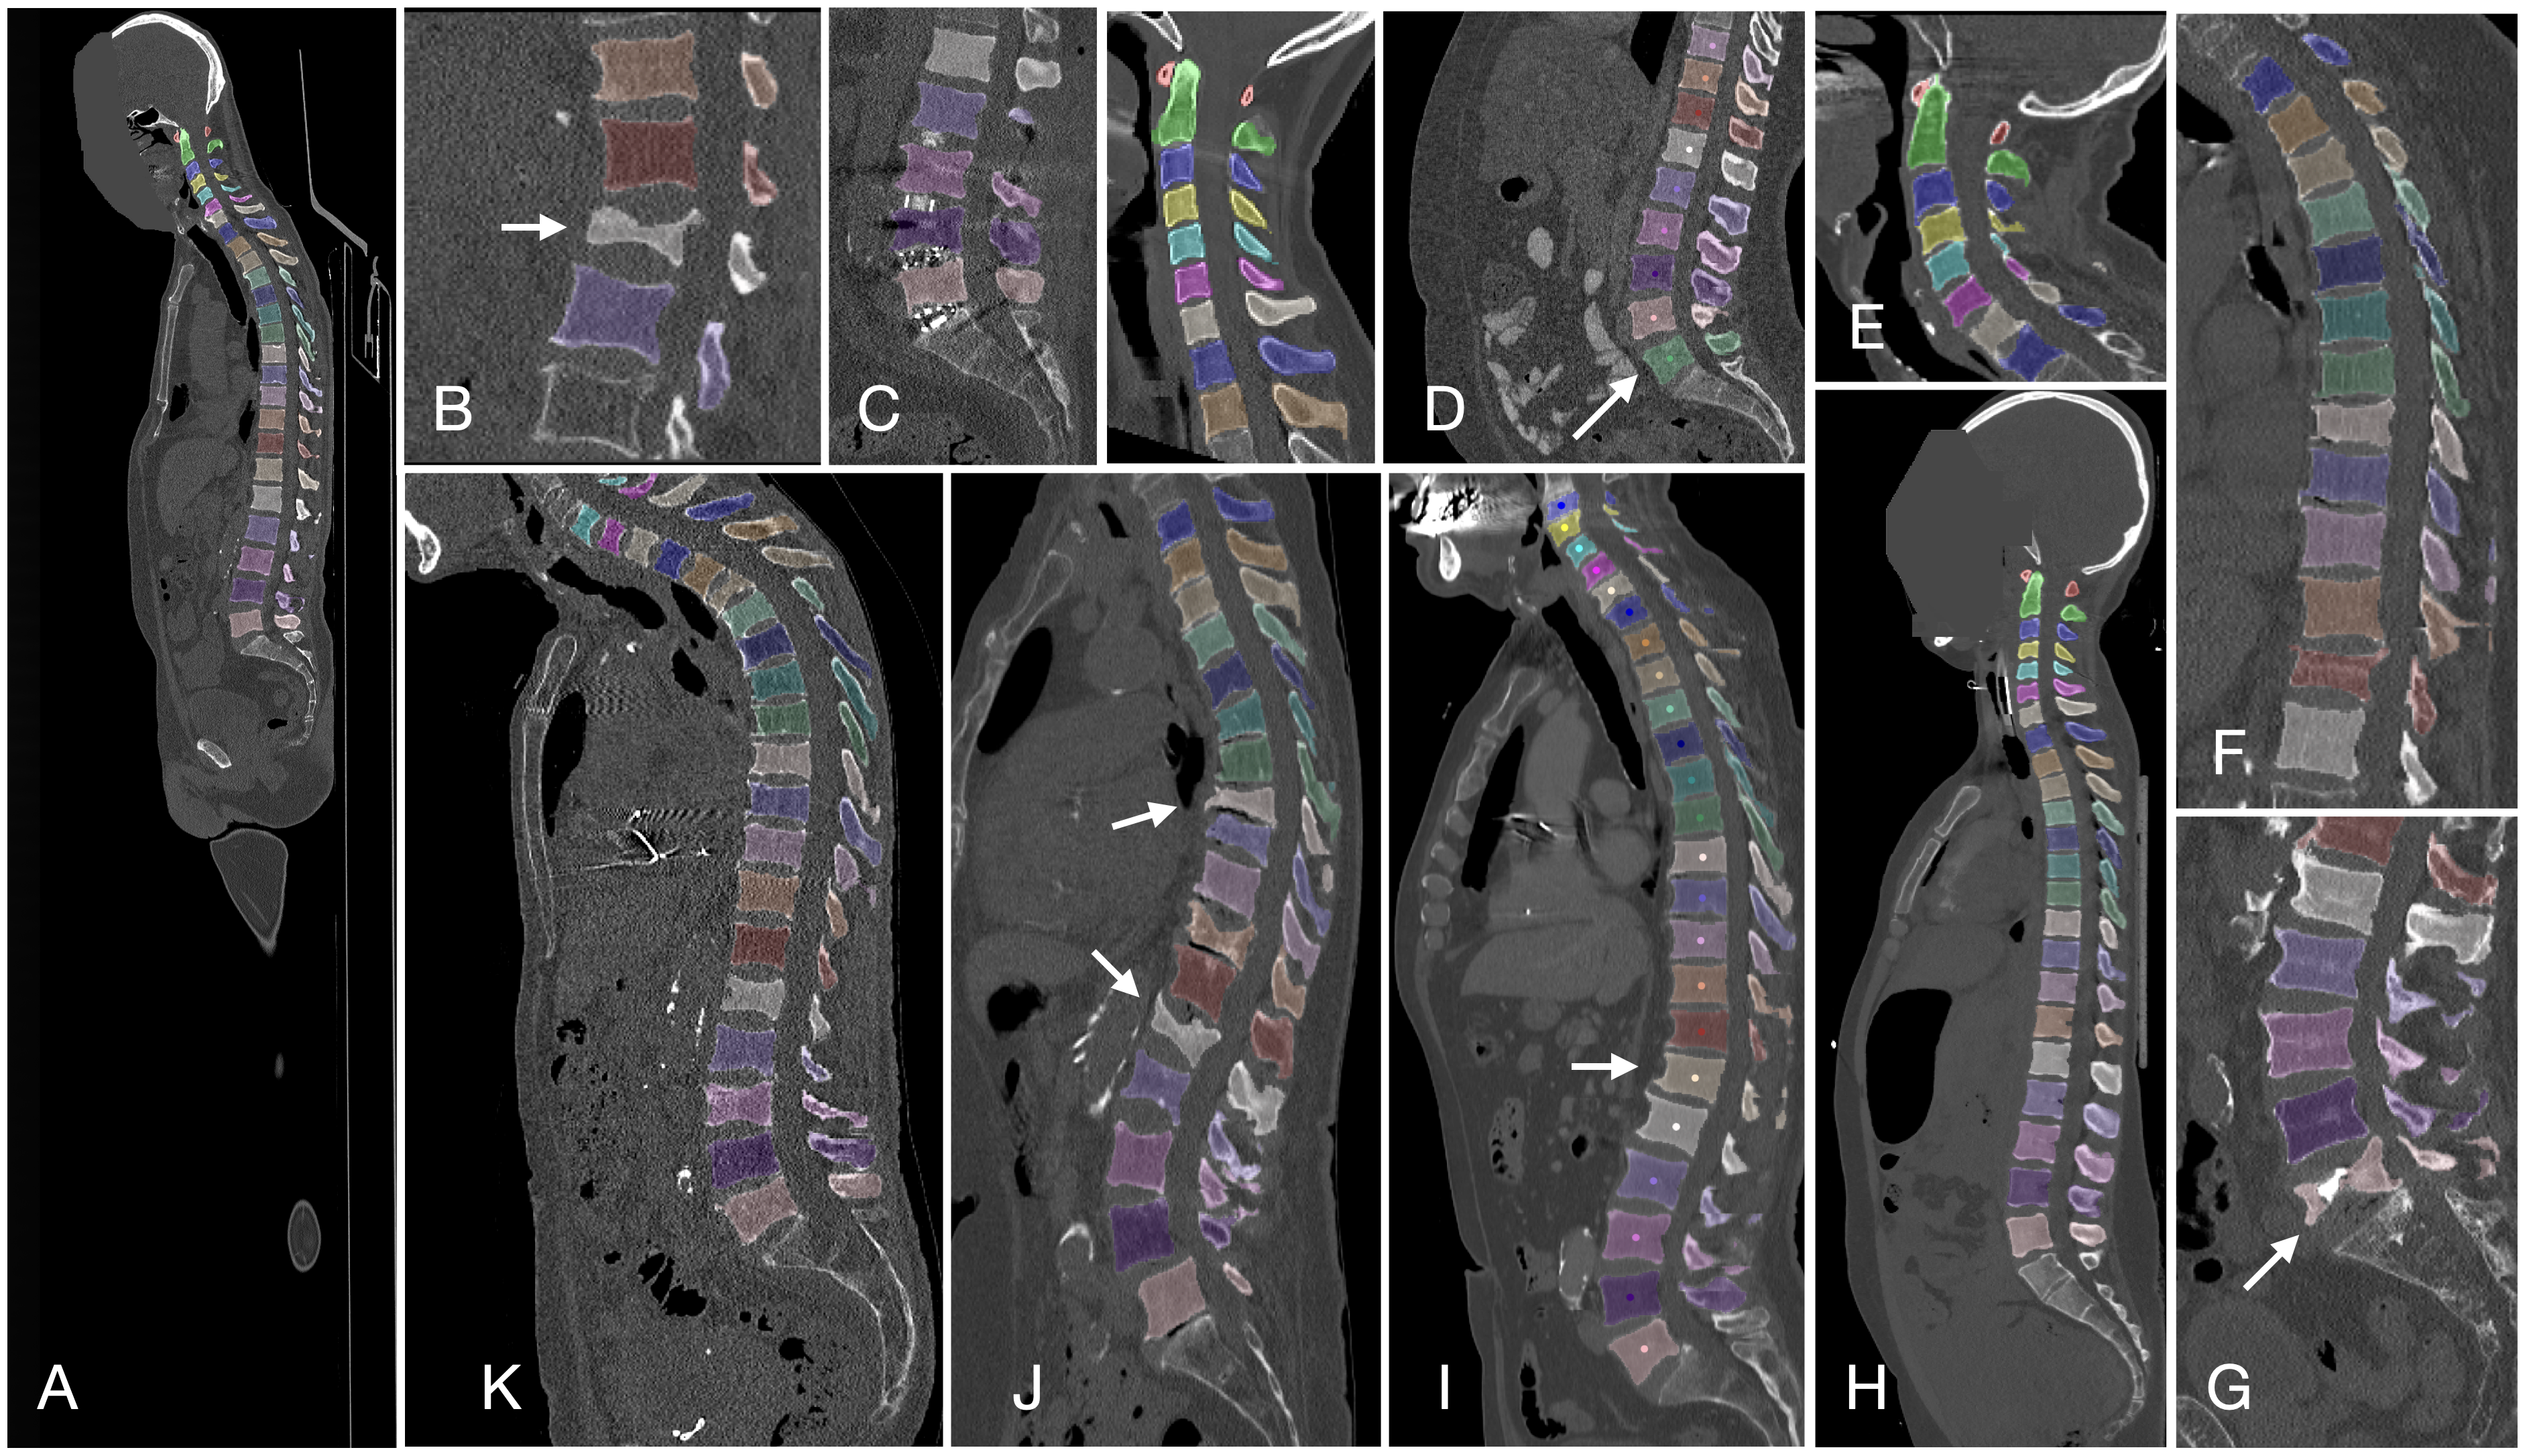

Verse大规模脊椎分割数据集

| VerSe | 脊椎 | 分割 | CC BY-SA 4.0 |